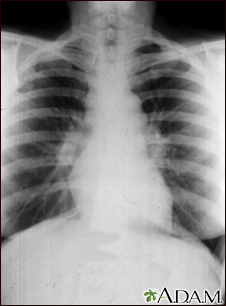

Sarcoid, stage I - chest x-ray